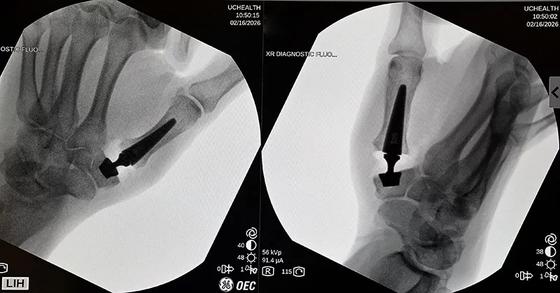

On February 16, 2026, CU Anschutz Orthopedics hand surgeons introduced a new surgical option for patients with advanced thumb carpometacarpal (CMC) arthritis performing the first joint preserving thumb prosthesis procedure in Colorado and the western United States

By contrast based on European experience with a new prosthesis the CU Anschutz team anticipates less post operative pain, faster recovery, and improved functional outcomes In Europe where the implant has been in use since 2018 patients often begin moving the thumb immediately post-surgery, with significantly less post surgical discomfort and a quicker return to daily activities.

KeriMedical Touch® CMC 1

Dual Mobility Trapeziometracarpal Prosthesis Courtesy of KeriMedical/Medartis

The new approach replaces the diseased joint with a small, dual mobility ball and socket prosthesis rather than removing the trapezium Instead of reconstructing the joint space with tendon, surgeons implant the device directly into bone preserving anatomy and maintaining the thumb’s natural biomechanics

By embedding the implant into the trapezium and first metacarpal, surgeons aim to reduce surgical trauma, maintain joint stability, and accelerate functional recovery while helping patients retain a more normal sense of thumb strength and motion. Following surgery, the first Colorado patient a 58 year old woman with osteoarthritis was able to go home the same day with only a soft dressing, avoiding the cast or prolonged splinting typically required after traditional CMC arthroplasty Early recovery mirrored outcomes reported by European surgeons, reinforcing expectations for a faster, less restrictive rehabilitation process.